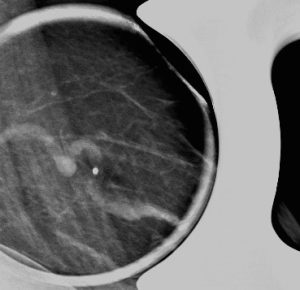

The spot magnification mammogram view and targeted ultrasound images that were performed at the site of palpable abnormality are shown here.

On our mammogram and ultrasound images, we can see the dilated and tortuous affected vessel. Although the vessel is abnormally hypoechoic under ultrasound due to the presence of thrombus, the presence of some color Doppler flow within the vessel indicates partial patency of the lumen.